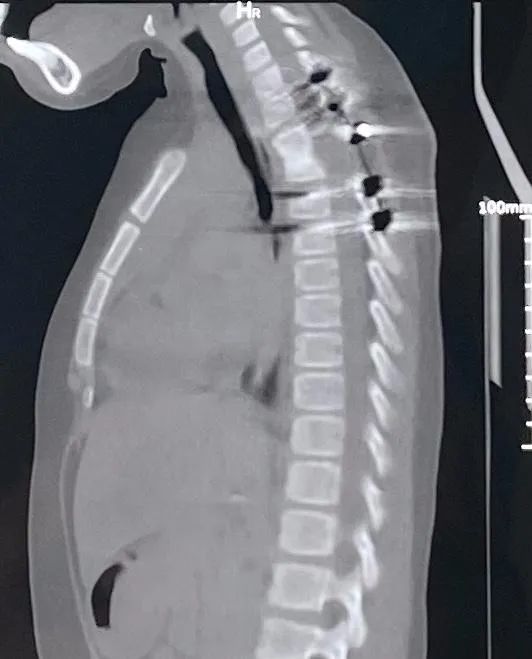

磁共振、CT 检查的结果显示第 2,3 胸椎骨质被结核菌侵蚀得千疮百孔,而且已经塌陷后凸,周围大量的脓液包裹着胸主动脉和脊髓,因而造成了病儿下肢瘫痪;而且病儿血沉很高、营养差、肝功能也不好。面对病情重、年龄小、体质差、时间紧一堆困难,脊柱外科迎难而上,果断决定尽早手术,清除死骨和脓液,矫正后凸畸形,挽救神经功能,否则病儿余生要在轮椅上生活了。科室组织全院会诊,儿科、感染科保障围手术期的用药,麻醉科、ICU、输血科保障手术的安全,医学影像科、胸心外科建言主动脉和胸膜的保护,护理组、康复组保障手术后的护理康复,群策群力为特殊的小病人付出最大关爱。

入院后第 3 天,谢宁主任带领王建杰和任亦龙主治医生实施了胸椎结核病灶清除重建手术,清除了死骨和脓液,手术中见到胸主动脉和脊髓都泡在脓液内,血管破裂会危及生命,十分凶险。考虑到病儿以后要生长发育,尽可能减少对其他部位骨头的干扰,利用剪下的肋骨作支撑,顺利完成植骨固定。护理和康复的姐姐们用玩具、贴纸哄小朋友吃药,做康复训练,病儿一家顺利地在除夕夜回到家乡。